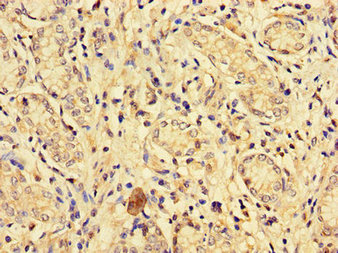

Immunohistochemistry of paraffin-embedded human gastric cancer using CSB-PA007720LA01HU at dilution of 1:100

Immunohistochemistry of paraffin-embedded human liver cancer using CSB-PA007720LA01HU at dilution of 1:100